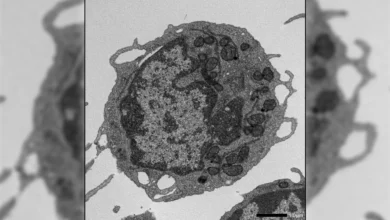

How aggressive breast cancer turns off the immune system

Breast cancer remains a formidable global health challenge, holding the somber distinction of being the most commonly diagnosed cancer among…